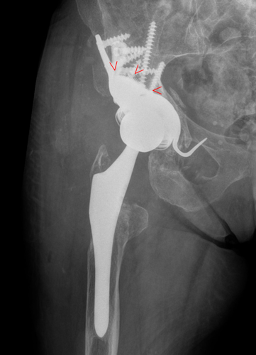

The postoperative unenhanced X-ray follow-up image now shows a normal implant position with good caudal positioning of the acetabular component compared to the preoperative findings and consecutive anatomical reconstruction of the normal hip rotation centre (Figure 11). The bony acetabular rim defect is bridged by the macrorough augmentation as planned and the caudal hook is positioned in the obdurator foramen.